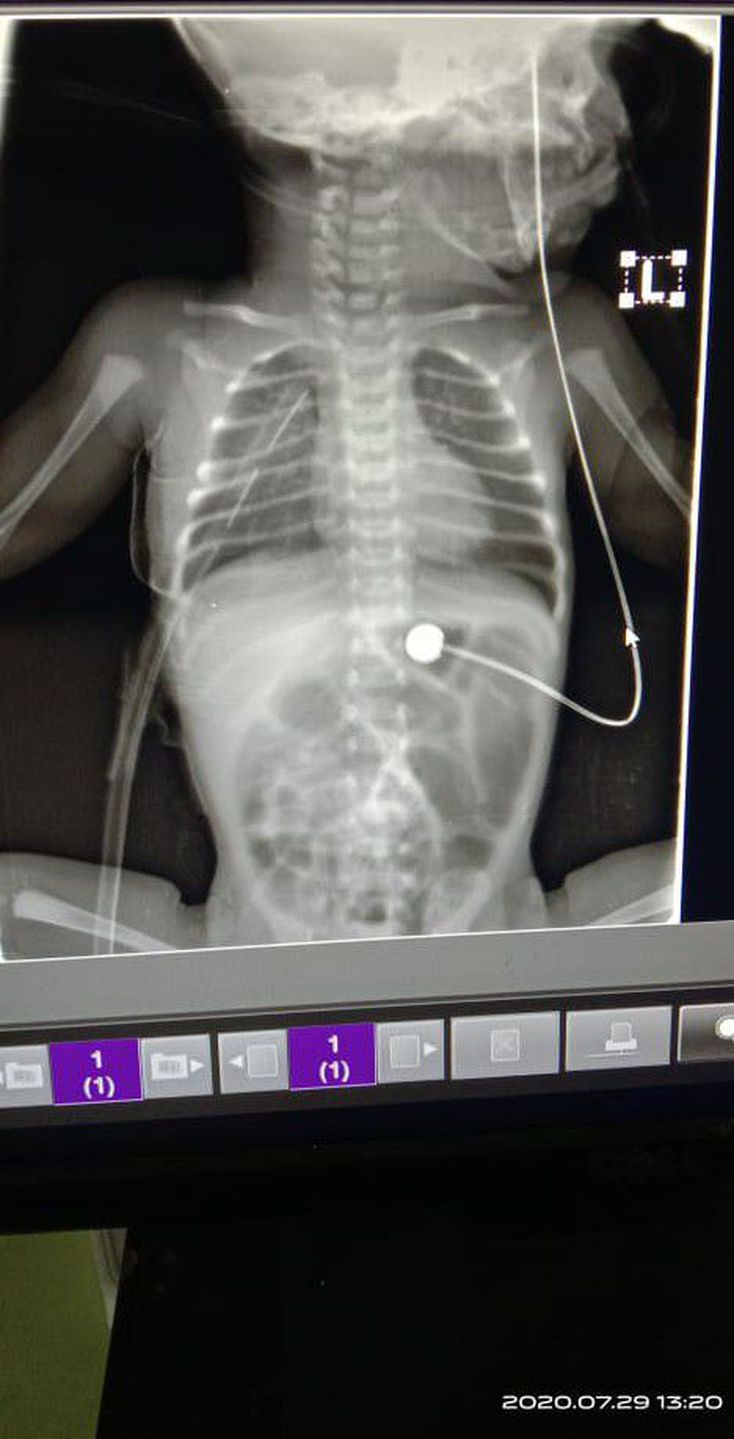

What is wrong with this kid?

Seems to have a chest tube!